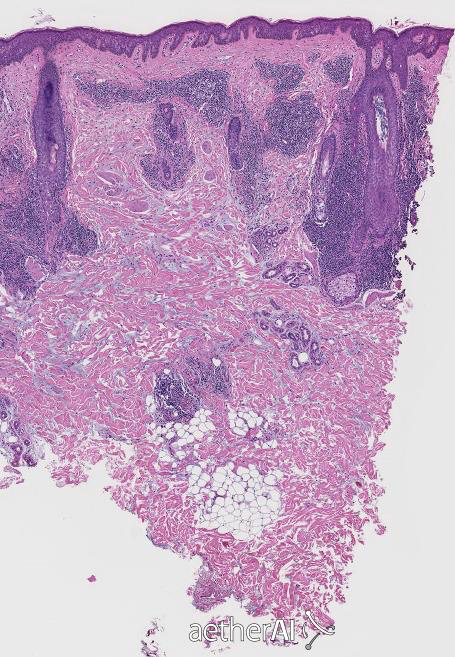

Scarring or non-scarring?

Scarring Alopecia

what are the features of scarring alopecia

* Loss of Sebaceous Glands * Presence of destructive inflammation or fibrosis around the follicles * Presence of compound follicles